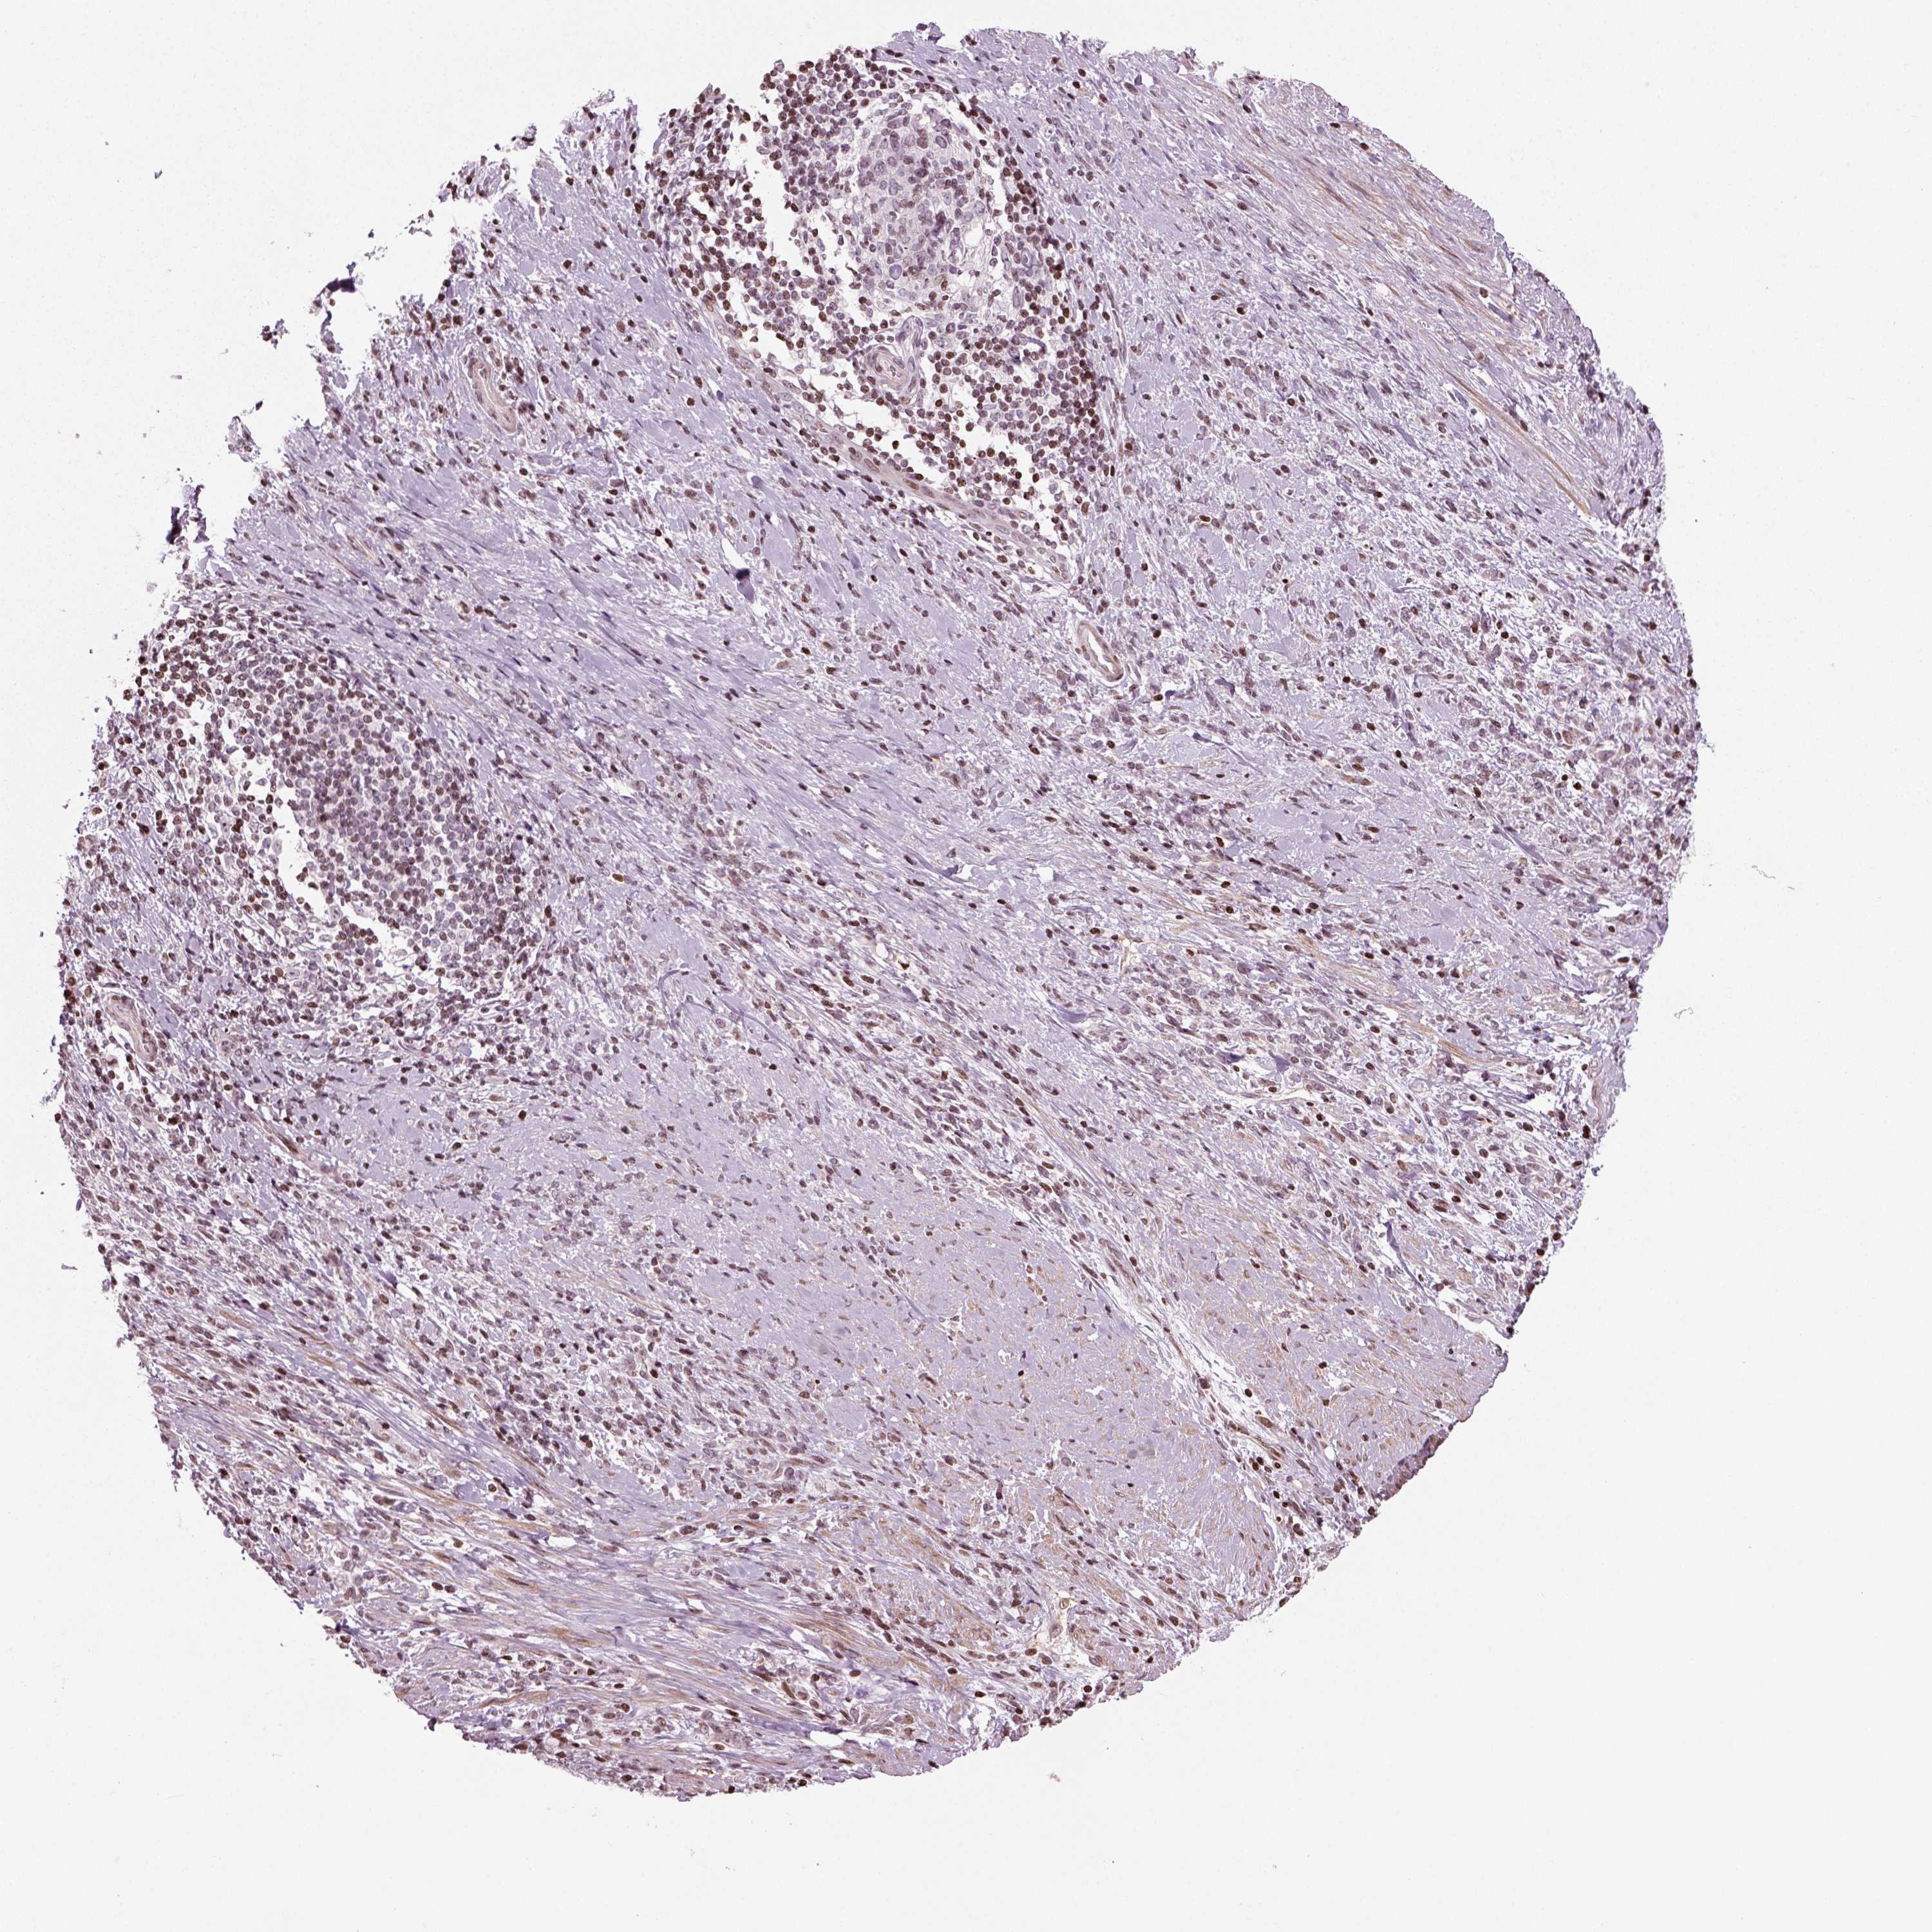

STOMACH CANCER - Protein expressioni

A mouse-over function shows sample information and annotation data. Click on an image to view it in a full screen mode. Samples can be filtered based on level of antibody staining by selecting one or several of the following categories: high, medium, low and not detected. The assay and annotation is described here.

Note that samples used for immunohistochemistry by the Human Protein Atlas do not correspond to samples in the TCGA dataset.

Antibody stainingi

Antibody staining in the annotated cell types in the current human tissue is reported as not detected, low, medium, or high, based on conventional immunohistochemistry profiling in selected tissues. This score is based on the combination of the staining intensity and fraction of stained cells.

Each image is clickable and will lead to virtual microscopy that enables deeper exploration of all samples and also displays staining intensity scores, fraction scores and subcellular localization as well as patient and tissue information for each sample.

Antibody HPA076960

Staining

High

Medium

Low

Not detected

Intensity

Strong

Moderate

Weak

Negative

Quantity

>75%

75%-25%

<25%

None

Location

Nuclear

Cytoplasmic/membranous

Cytoplasmic/membranous,nuclear

Adenocarcinoma, NOS